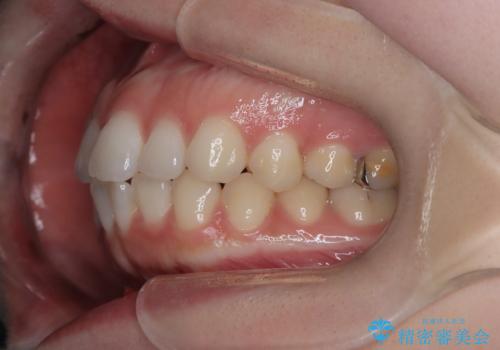

審美ワイヤー矯正とTAD併用による犬歯の遠心移動

- 歯並びの乱れを改善したいと来院されました。精密検査の結果、犬歯を奥へ動かすことで、より美しい口元と安定した咬み合わせが得られると診断。患者様のご希望から、目立ちにくい審美ワイヤー矯正を採用し、効率的な歯の移動のために**リンガルアーチとTAD(矯正用アンカースクリュー)**を併用する計画を立てました。これにより、抜歯せずにスペースを確保し、犬歯をスムーズに遠心へ移動させます。